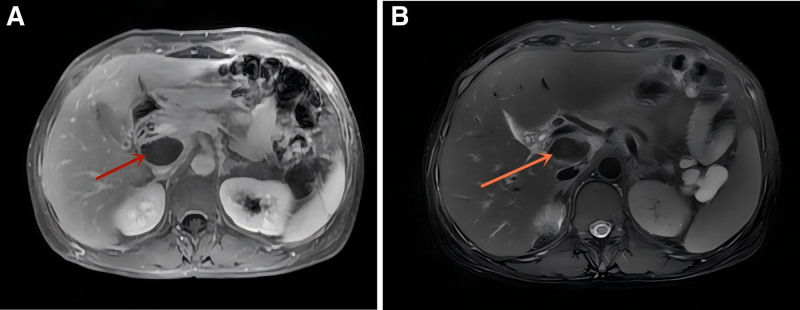

Patient concerns: A 48-year-old woman initially presented with abdominal pain, back pain, and constipation, which were managed as gastrointestinal disorders. Her condition progressed rapidly to include severe cardiac symptoms, including chest tightness and dyspnea.

Diagnoses: Cardiac magnetic resonance imaging revealed findings indicative of AC, including left ventricular hypertrophy, diffuse delayed enhancement, and atrial enlargement. The diagnosis of immunoglobulin light chain amyloidosis was confirmed by endomyocardial biopsy, which was positive for κ light chains.